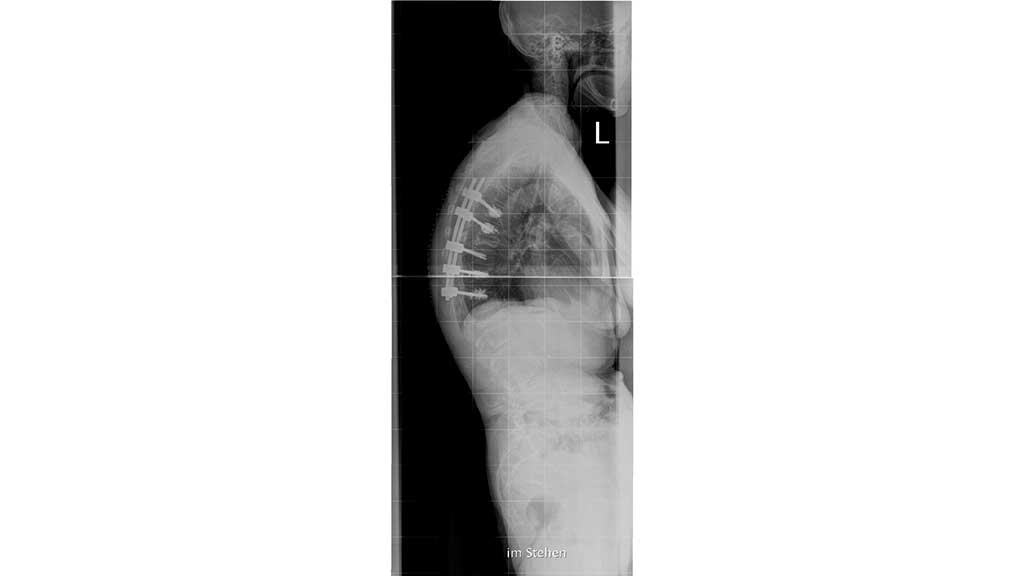

Eine häufig auftretende Begleiterscheinung der Osteoporose ist die Sarkopenie. Geprägt von einem degenerativen, altersbedingten Verlust von Muskelmasse, ‑kraft und ‑funktion hat auch diese Erkrankung weitreichende Folgen, die unter anderem mit einer Erhöhung des Sturzrisikos und dem Auftreten funktioneller bzw. motorischer Einschränkungen einhergehen. Von besonderer Bedeutung ist jedoch das Zusammenspiel beider Erkrankungen, vornehmlich im Hinblick auf die Wechselwirkungen von Knochen und Muskel. Einerseits kommt es durch die Sarkopenie durch mangelnde und falsche Beanspruchung des muskuloskelettalen Bewegungssystems zu arthromuskulären Defiziten sowie zu Dysbalancen, die wiederum über Verspannungen, Myogelosen und Blockierungen zu Schmerzen führen können. Andererseits ist durch die Sarkopenie das Sturzrisiko der Patienten deutlich erhöht, was das Auftreten von Frakturen bei ohnehin geschwächtem Knochen begünstigt. Die Frakturen machen häufig operative Stabilisierungen nötig (Abb. 2).